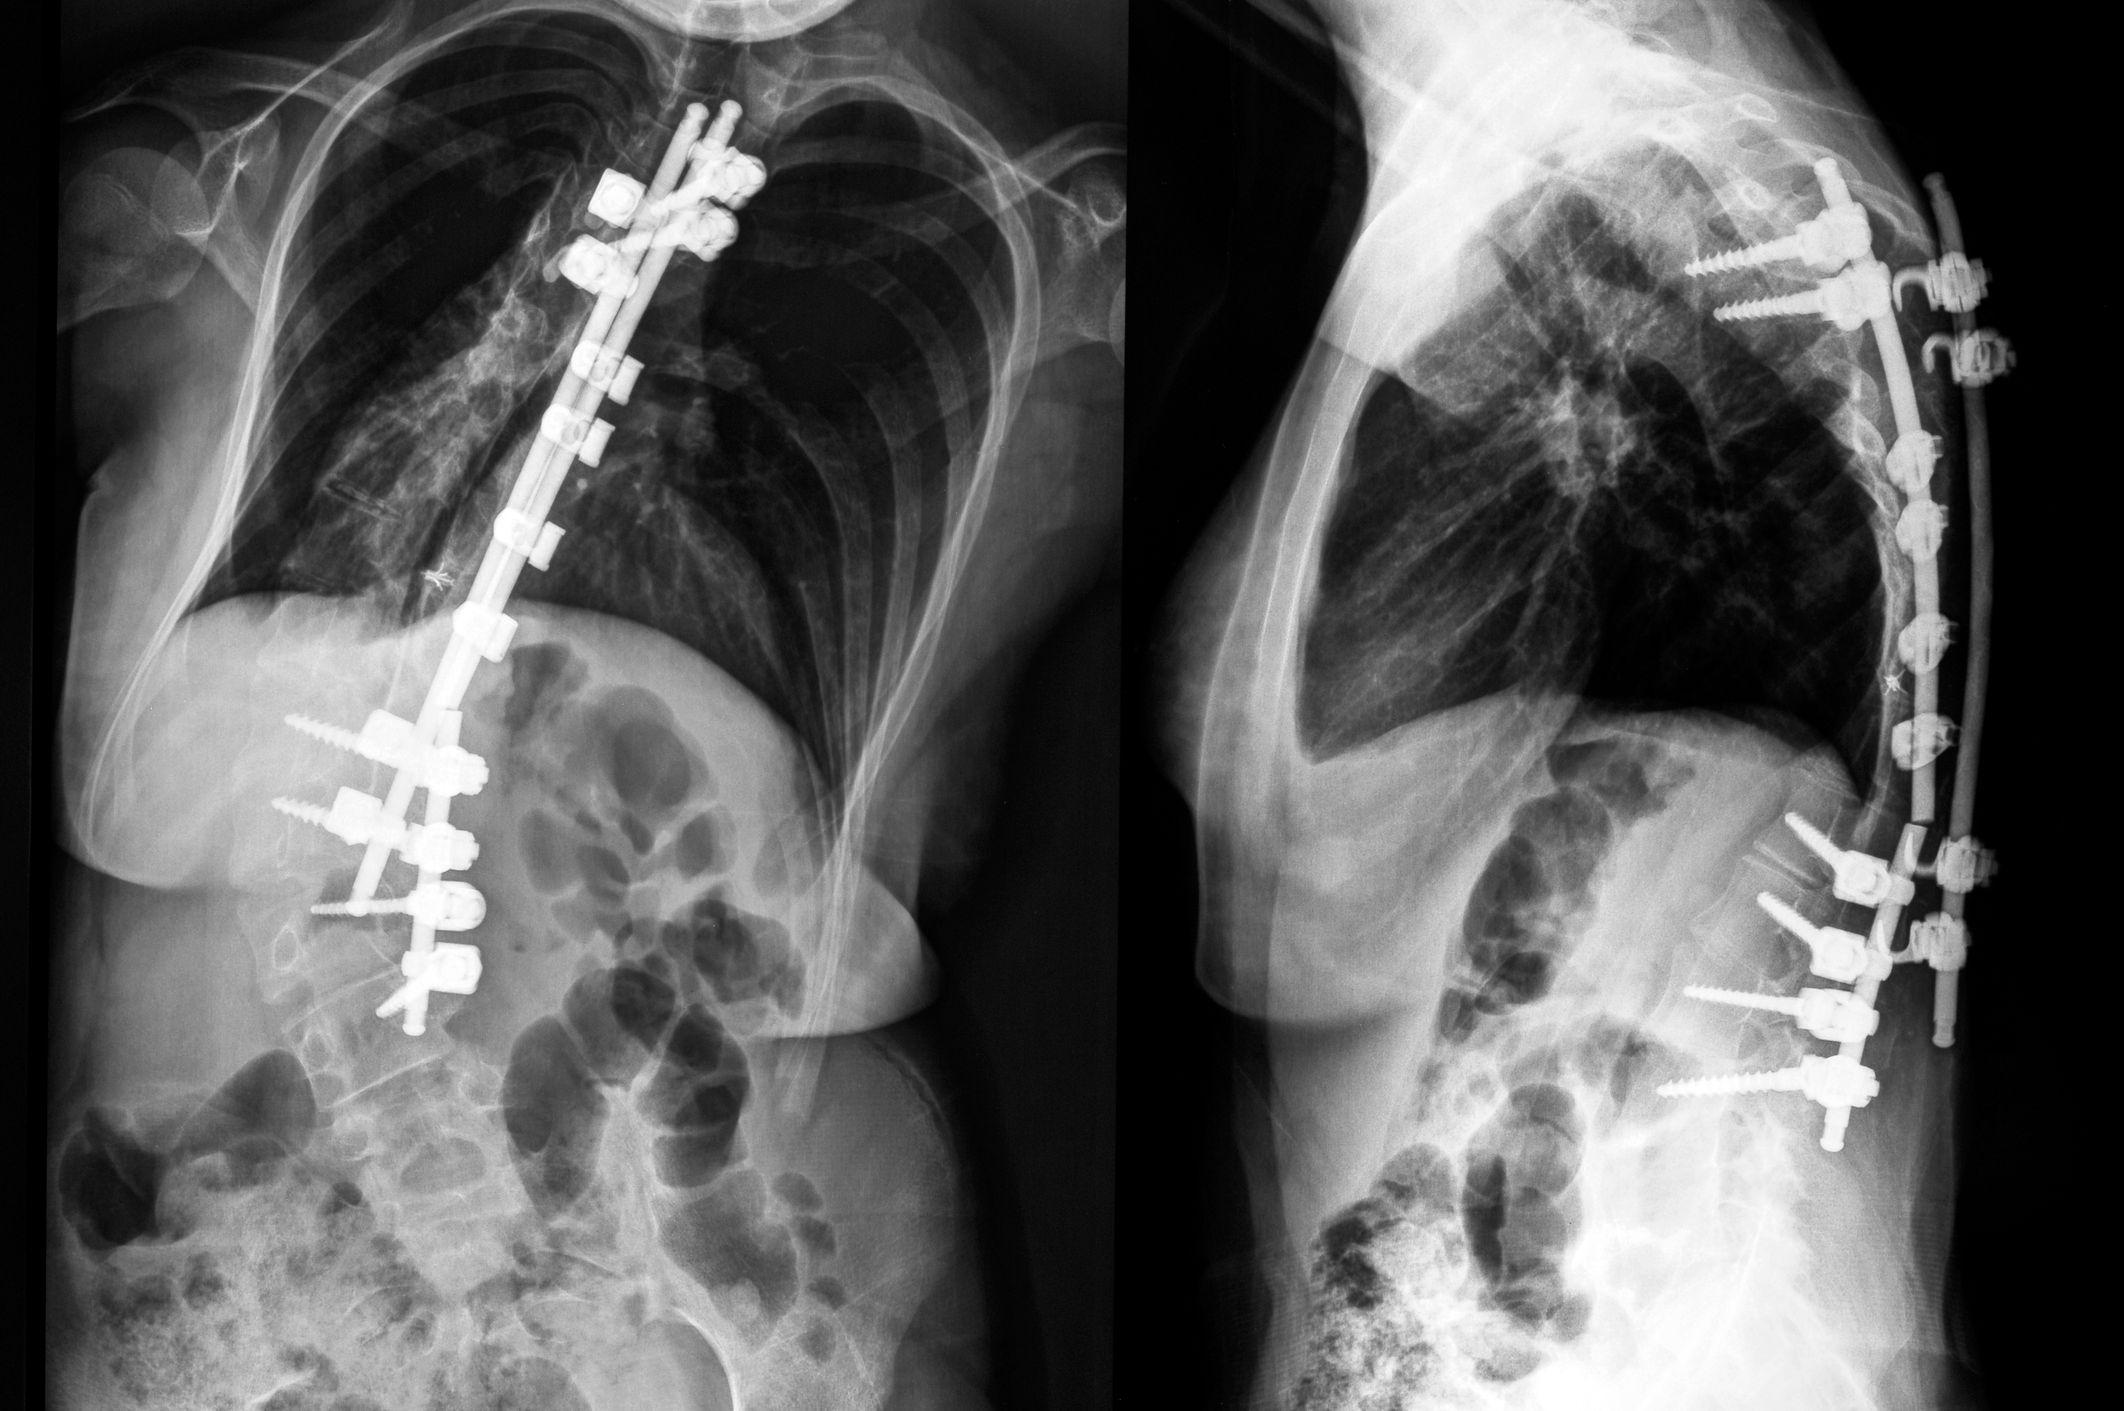

Failed Back Surgery Syndrome: Why It Happens and How to Fix It